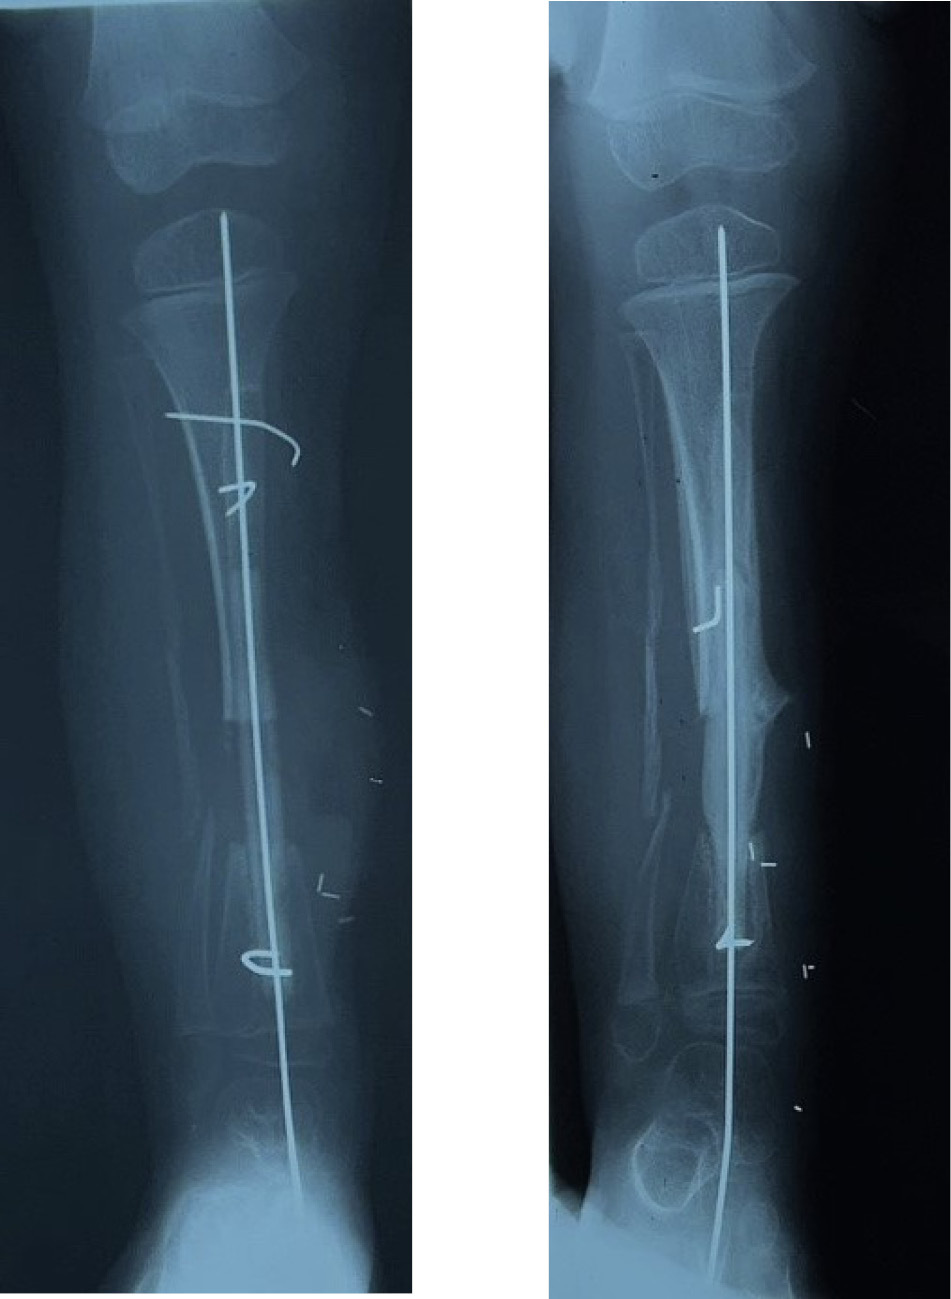

Another form of fixation is an intramedullary nail or rod used in two of our nine cases of resection of a pseudarthrosis of the tibia in a child shown in Cases 12 and 13 (Figures 32 and 33). In these two cases, the distal tibial fragment could not be fixed to the fibula with a screw. Instead a Rush nail was passed from below through the heel, calcaneum, talus and distal tibia and into the medullary cavity of the transplanted fibula. The result was exactly the same as the other seven cases. Even in plaster you can’t keep a child still! By six weeks all, including the two with nails, showed union and early bone hypertrophy (Figures 32 and 33).